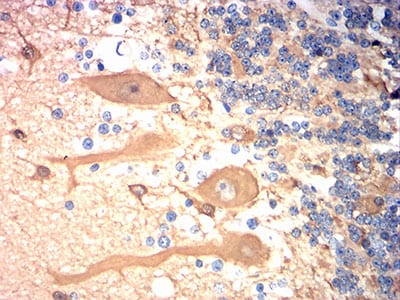

| IHC | 1/200 - 1/1000 | Human,Mouse,Rat |

The TUBB3 antibody targets the βIII-tubulin protein, encoded by the TUBB3 gene, which belongs to the β-tubulin family. βIII-tubulin is a neuron-specific isoform predominantly expressed in developing and mature neurons, where it plays critical roles in axonal guidance, neuronal migration, and cytoskeletal dynamics. Unlike other β-tubulins, TUBB3 is associated with specialized microtubule functions in nerve cells, influencing neurogenesis, plasticity, and intracellular transport.

TUBB3 antibodies are widely used in research and diagnostics to identify neuronal populations, assess neurodevelopmental or neurodegenerative conditions, and characterize neural tumors (e.g., neuroblastomas). Overexpression of βIII-tubulin is also linked to aggressive cancer phenotypes and resistance to microtubule-targeting chemotherapeutics, making it a biomarker in oncology. However, TUBB3 mutations are implicated in rare congenital disorders, such as cortical dysplasia and ocular motility defects, highlighting its clinical relevance.

Validation of TUBB3 antibodies requires attention to specificity due to structural homology among tubulin isoforms. Applications include immunohistochemistry, Western blotting, and flow cytometry. Its dual role in neuronal health and disease underscores its importance in both basic neuroscience and translational medicine.